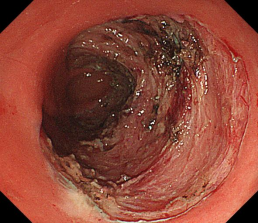

肝硬化食管、胃底静脉曲张破裂出血TIPS介入治疗

肝硬化门脉高压的tips治疗